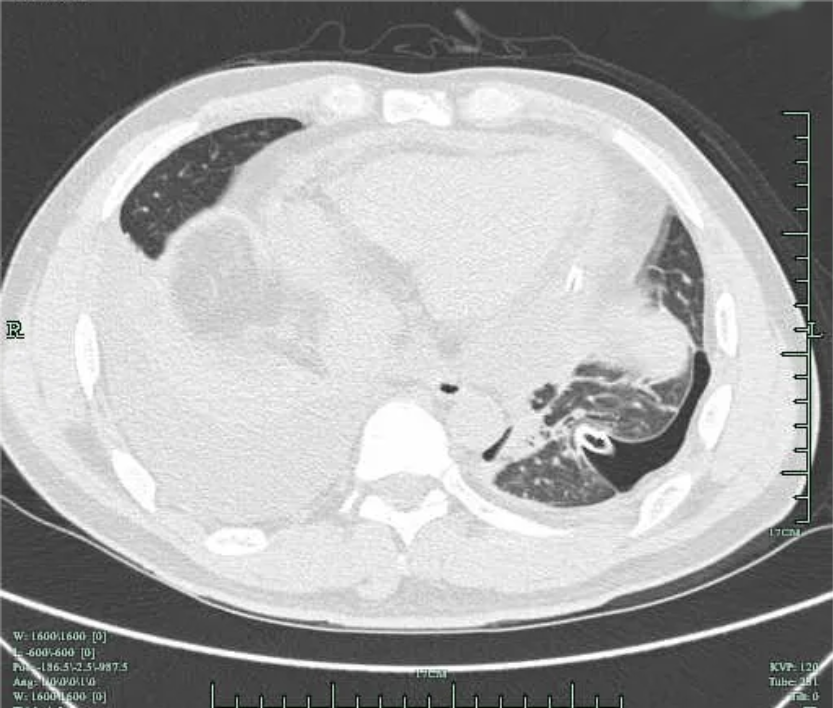

患者3周(2022年10月10日)前出现左前胸及侧胸疼痛,呈阵发性隐痛,能忍受,疼痛无放射性,否认疼痛时黑曚、汗出、否认畏寒发热等,社区医院用药(具体药名不详)后好转;1周前(10月23日)左侧胸部出现压榨痛,疼痛呈持续性不能缓解,伴胸闷气急,至县医院就诊:血常规:白细胞 11*10^9/L(3.5-9.5*10^9/L),血红蛋白及血小板正常;超敏C反应蛋白:67.95mg/L(0.00-3.30mg/L),心电图示:V2-V5导联ST段凹面向上稍抬高(图1);10月24日肺部CT示(图2):左肺散在炎症,左侧胸腔少量积液伴邻近肺组织膨胀不全,两肺散在纤维灶,心包积液,升主动脉增宽;10月24日心超示:三尖瓣反流,左室舒张功能减低,心包积液(心尖部心包分离约0.5cm),心动过速,EF:57%。

图2 肺部CT 肺窗提示 右侧胸腔积液,左侧胸腔积液引流后改变

住院过程中,追问患者为面馆老板,否认食用生鱼、醉虾、醉蟹等,回忆起患病前1周曾有一次修理摩托车过程中遭低压(220V)电击,当时有左侧胸痛,全身麻刺感,随后隐约觉得左侧胸痛,刺痛或隐痛,未重视;此次入院后经抗感染、胸水引流、心包积液引流等处理,复查胸水明显减少,心包积液减少,约半年随访复查肺部CT 两肺未见实质性病灶(图5),未见胸腔积液,未见心包积液,故此次胸腔积液及心包积液考虑低压电击后心肌损伤,胸部钝挫伤、血胸可能。

图5 2022-12-8复查肺部CT 两侧胸腔积液完全吸收,两肺未见实质性病灶。